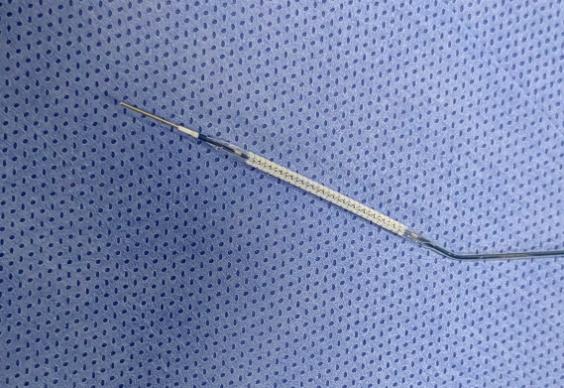

目前,绝大多数的冠心病患者植入的都是第三代金属药物洗脱支架,因其“金属”特性而存在一定的弊端。生物可吸收支架则采用完全可降解聚合物材料聚乳酸(PLLA)作为支架基体材料,其涂层为含有雷帕霉素的生物可降解高分子材料,植入人体后经过血运重建、支架降解吸收和血管修复三个阶段,历经3年左右的时间在体内完全降解为水和二氧化碳,不仅避免了金属支架永久残留体内带来的风险,而且还使血管的弹性舒缩功能得到恢复,真正实现了从“血管再通”到“血管再造”的飞跃。

图1 生物可吸收支架